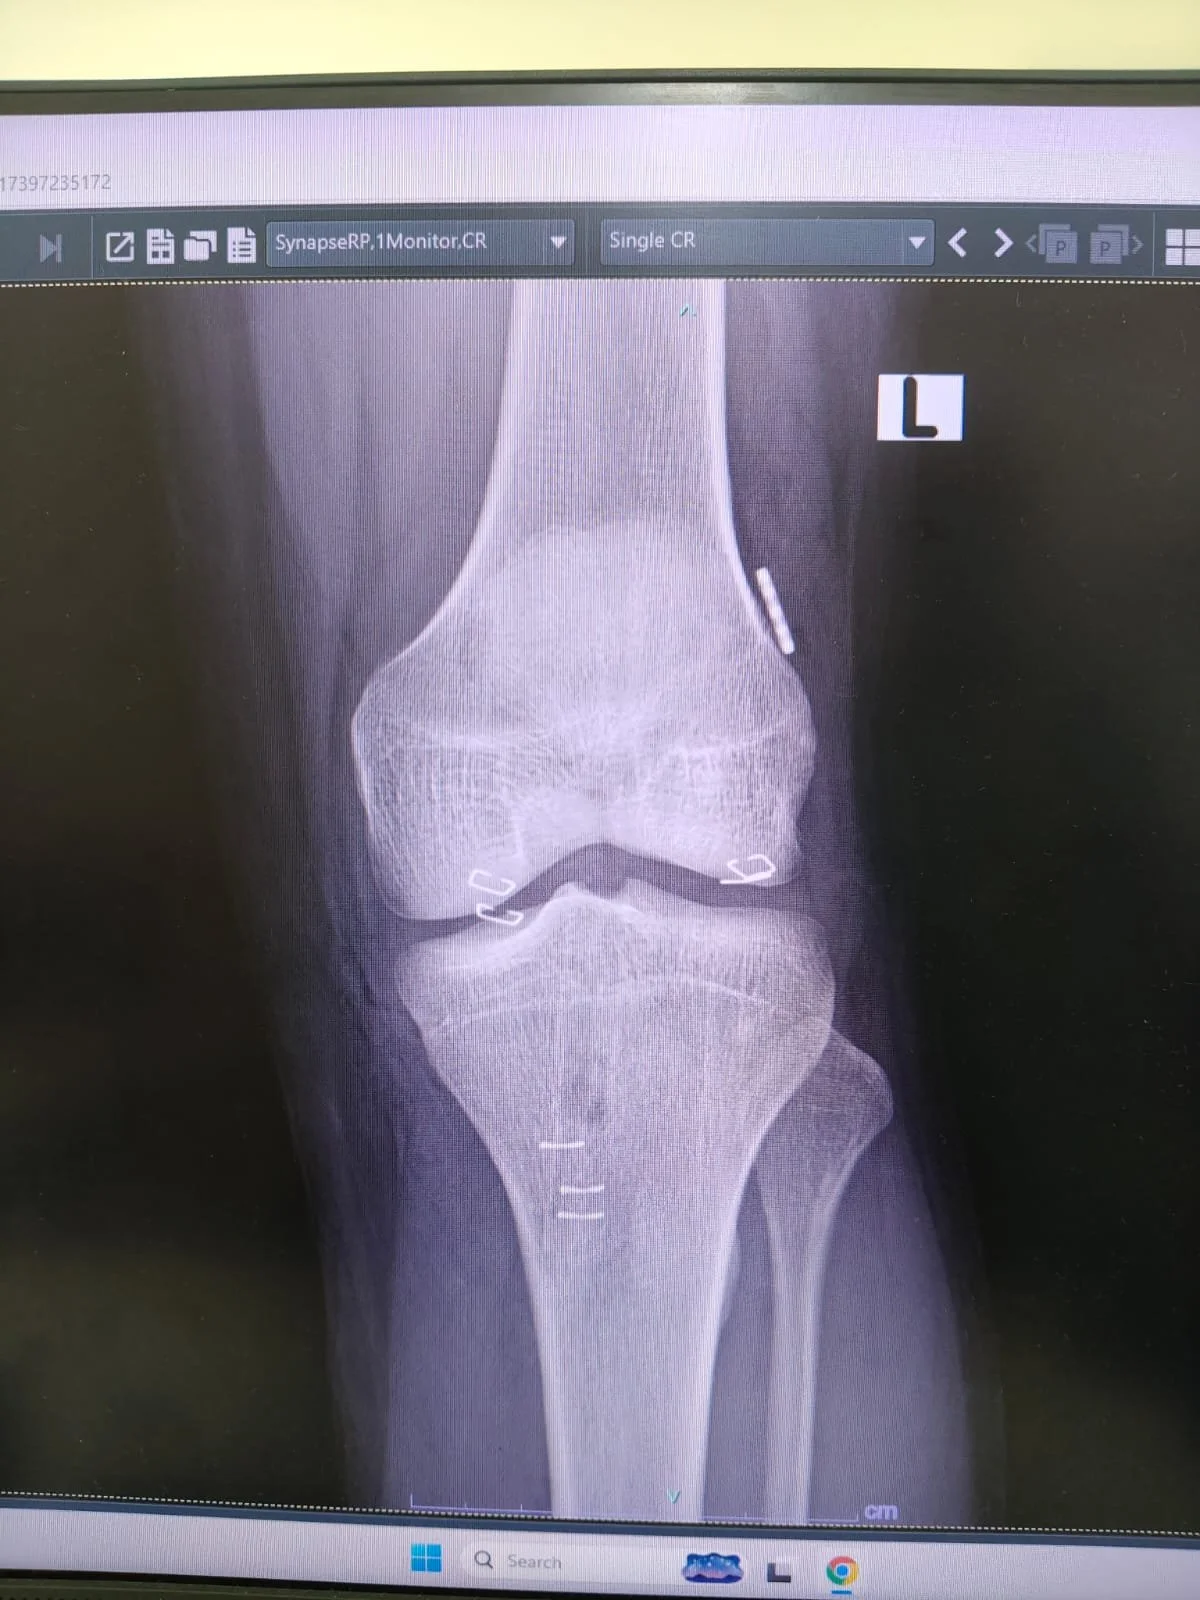

Arthroscopy & Sports Injuries

Minimally invasive keyhole surgery for ligament tears, meniscus injuries, and shoulder problems. Faster recovery, smaller scars, back to activity sooner.